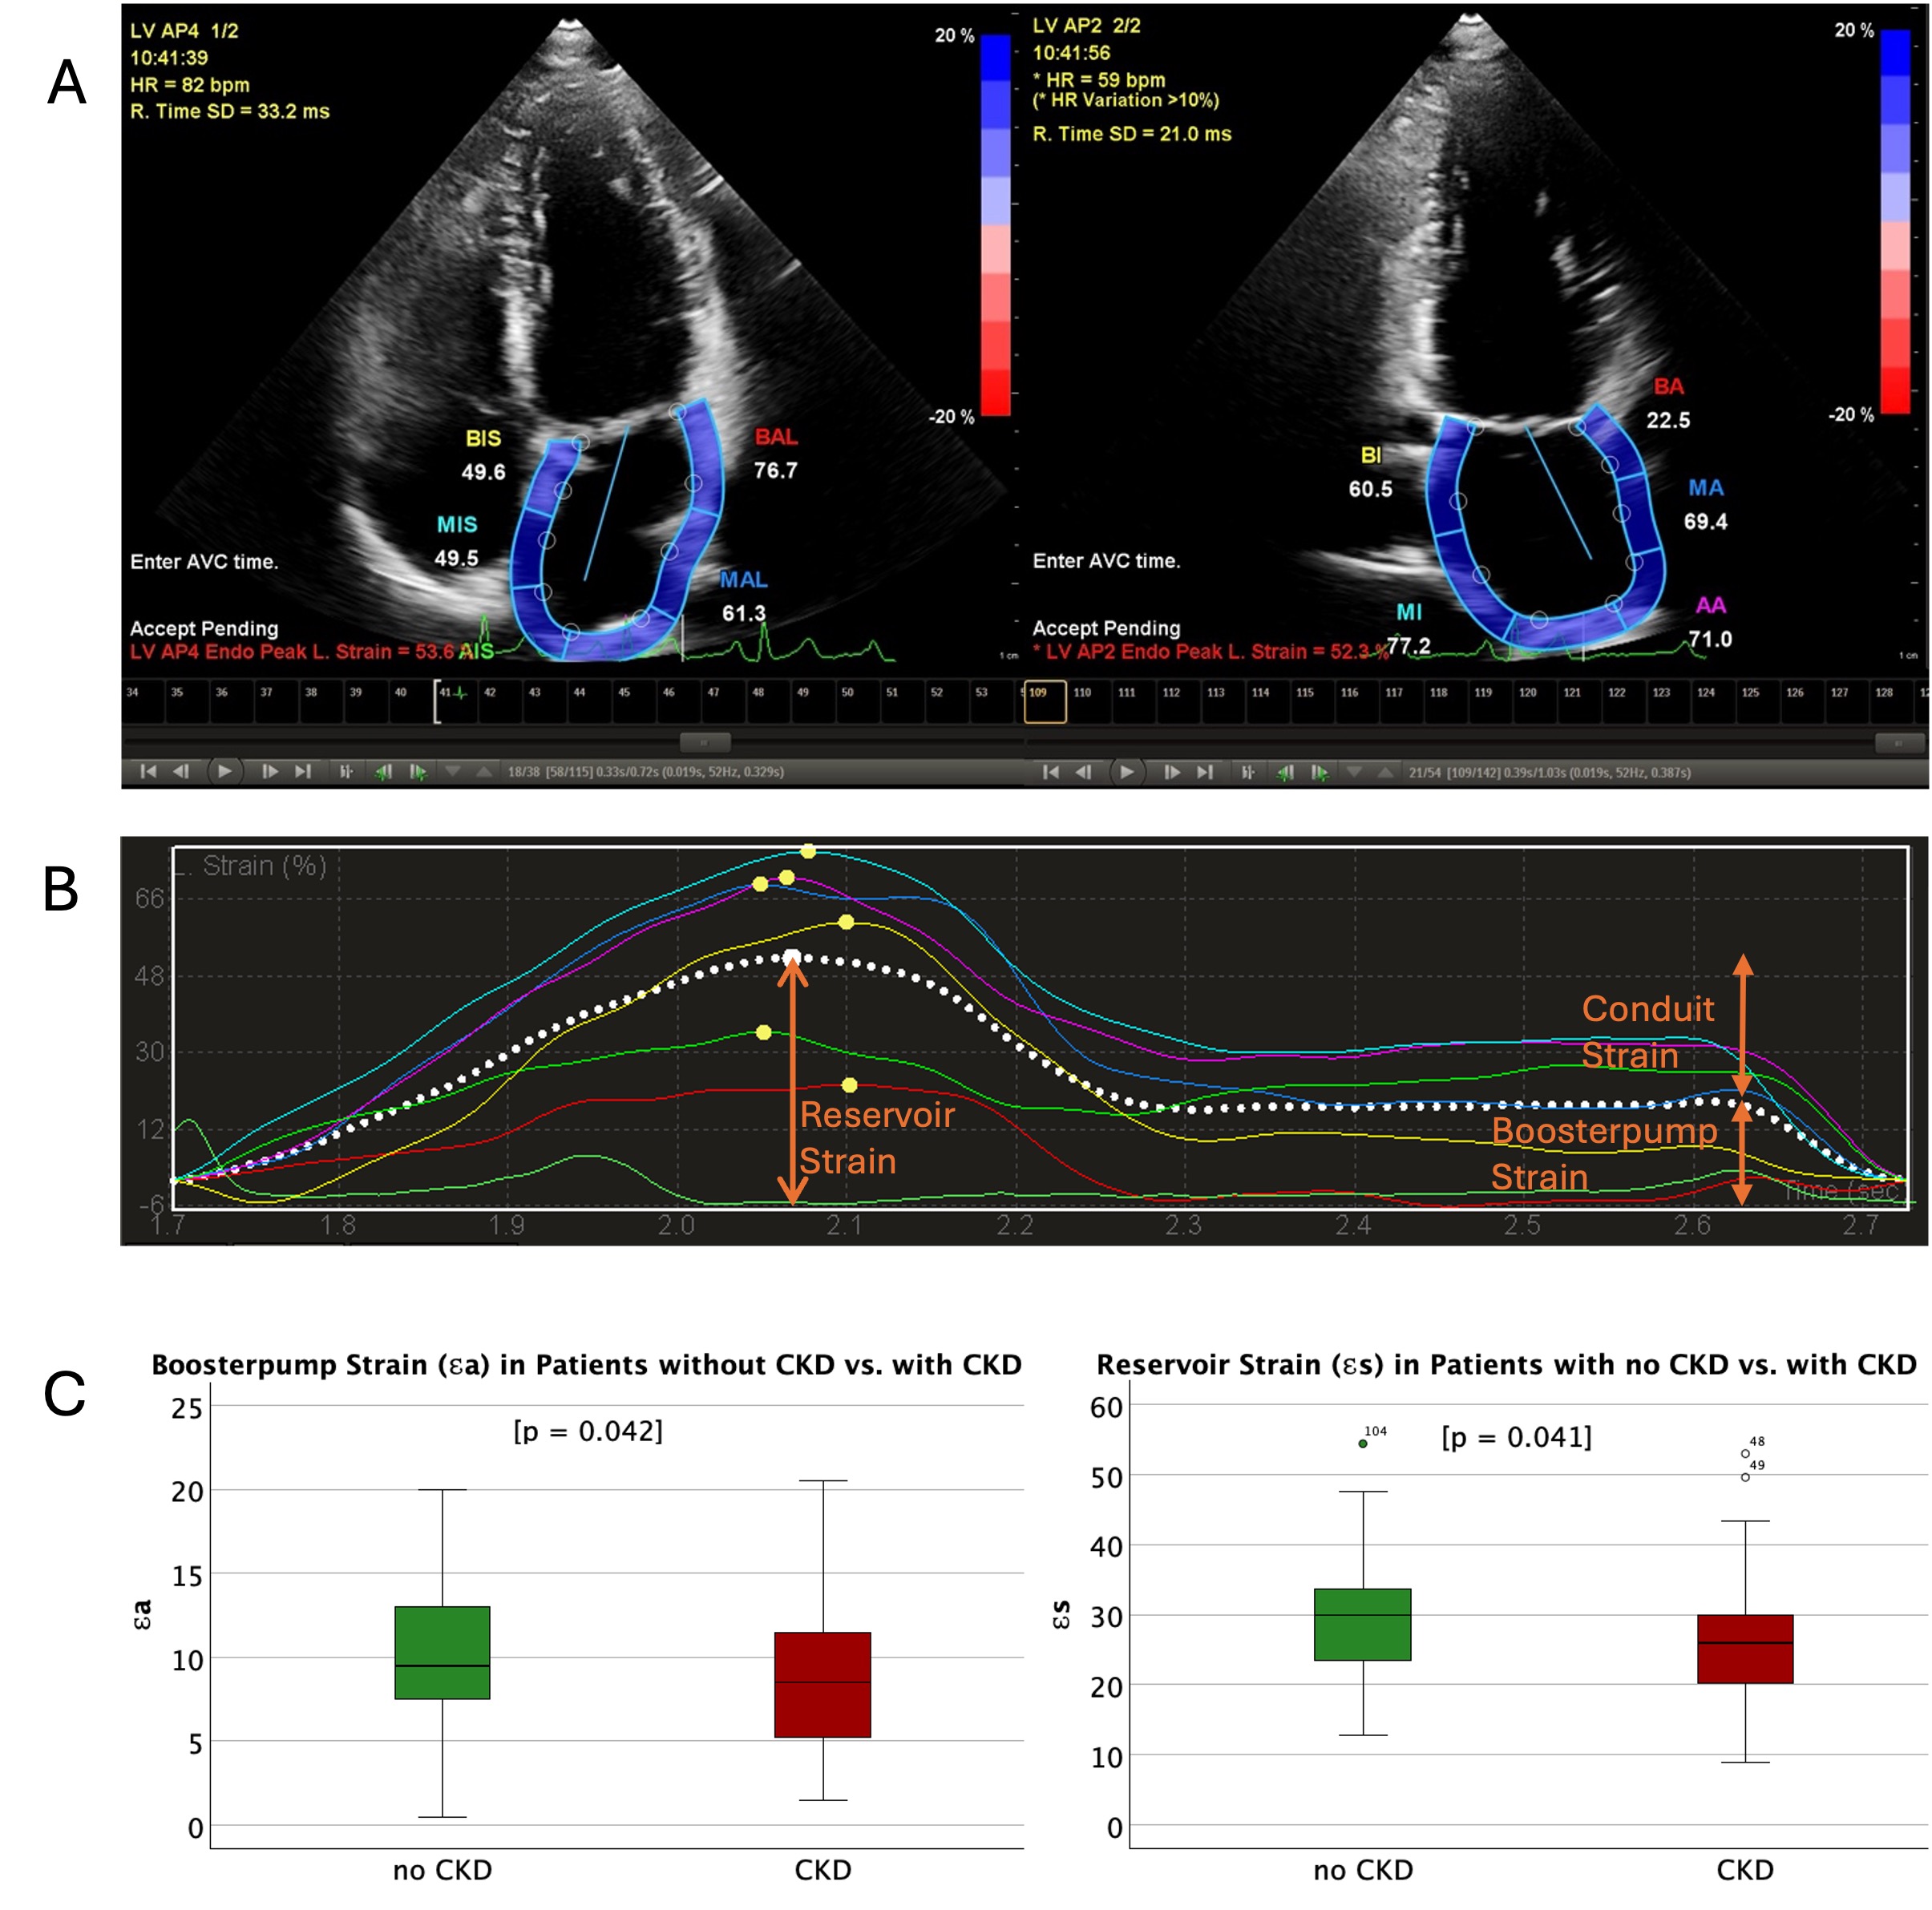

Asymptomatic patients (NYHA≤I) with preserved left ventricular ejection fraction (LVEF)≥50%, absence of cardiomyopathies and severe valve disease but at risk for HFpEF (age≥60 years, arterial hypertension (RR≥140/90 mmHg or ≥two antihypertensives), diabetes mellitus, history of atrial fibrillation, obesity (body mass index≥30 kg/m2), chronic kidney disease) were prospectively enrolled from internal medicine outpatient departments. Patients with an established diagnosis of HFpEF were excluded. All patients underwent structured clinical assessments including anamnesis, transthoracic echocardiography and laboratory testing. LA strain analyses were conducted via Philips Q-Station (Version 3.8.5) on apical two- and four-chamber views (Fig. 1). LA strain values were manually derived from strain curves. Renal function was calculated using the 2021 CKD-EPI equation to estimate glomerular filtration rate (eGFR). CKD was defined as an eGFR<60 ml/min/1.73m2 or urinary albumin/creatinine ratio (uACR) ≥30mg/g.

However, patients with CKD had decreased LA booster pump strain (Ɛa) and reservoir strain (Ɛs) compared to patients without CKD. (Ɛa: 8.0% (4.8;11.8) vs. 9.5% (7.0;13.0), p=0.042 and Ɛs: 24.6% (19.9;30.8) vs. 30.0% (23.3;34.5), p=0.041) (Fig. 1).

Fig. 1: Comparison of LA strain in patients with and without CKD. (A) Example of LA strain analysis in apical four- and two-chamber view. (B) Resulting LA strain curve including reservoir, conduit and booster pump strain. (C) Boxplots (median with interquartile ranges (IQR) and whiskers defining 95% Confidence Interval) of booster pump and reservoir strain in patients with and without CKD. A p<0.05 indicates statistical significance. CKD – chronic kidney disease, LA – left atrium.